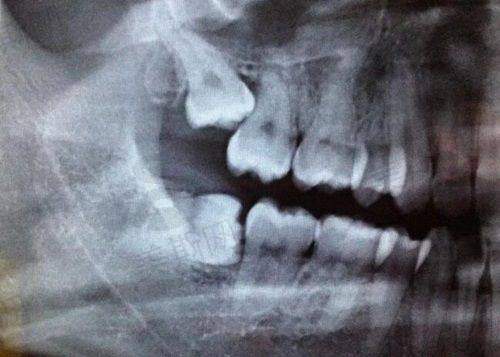

苏州英博口腔采用了精良的种植牙技术,如数字化口腔扫描、3D 打印导板、即刻种植牙技术。数字化口腔扫描可以严谨获取患者口腔的三维数据,医生可以在电脑上进行模拟种植,提前规划种植位置和角度,提高手术的精度。

3D 打印导板则是根据模拟种植的结果制作而成,在手术中可以为医生提供正确的引导,使种植体能够正确地植入到预定位置。即刻种植牙技术可以在拔牙后立即进行种植,减少患者的等待时间,缩短治疗周期。